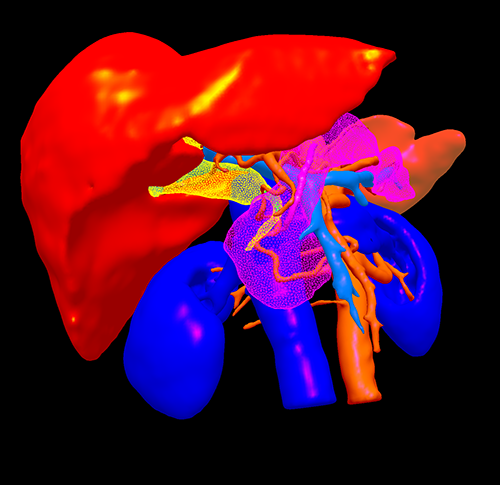

胆总管下端癌--胰十二指肠切除